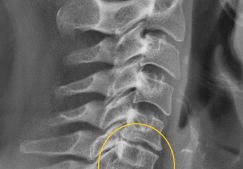

Мануальная терапия при остеохондрозе шейного отдела: показания и противопоказания к применению

Что представляет из себя мануальная терапия при остеохондрозе шейного отдела, показания и противопоказания к применению данного способа лечения.